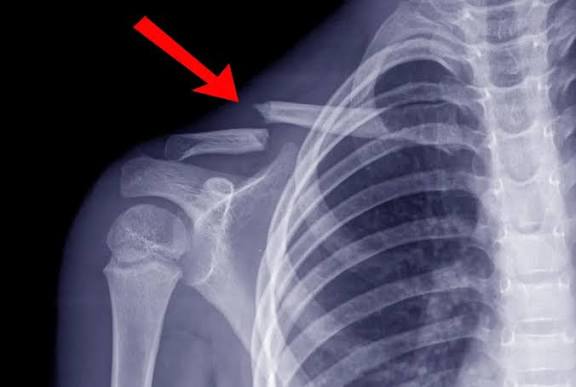

كيف يتم تشخيص كسر الترقوة؟

يبدأ التشخيص بفحص سريري يتبعه تصوير بالأشعة السينية لتحديد:

ـ مكان الكسر

ـ نوعه

ـ مدى انفصال الأجزاء

وفي الحالات المعقدة يستخدم الأطباء الأشعة المقطعية قبل وضع خطة العلاج.